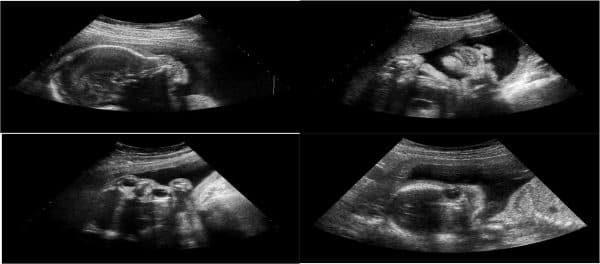

Siêu âm lần cuối trước khi sinh có thể nói là dấu mốc vô cùng quan trọng cho việc vượt cạn của mẹ. Không chỉ có mục đích kiểm tra, đánh giá tổng thể thể chất của thai nhi, việc siêu âm cũng giúp bác sĩ có thể sớm phát hiện những bất thường mới xuất hiện ở cả mẹ và con. Vậy cụ thể mục đích của siêu âm khi sinh hay những lưu ý khi chuẩn bị thực hiện siêu âm là gì?

Từ tuần thứ 36 trở đi được tính là giai đoạn cuối của thai kỳ, thời điểm này mẹ bầu nên đặt lịch khám thai với chu kỳ 1 lần/ 3 ngày để có thể theo dõi sát sao sự phát triển của thai nhi đồng thời kiểm tra chắc chắn không có dấu hiệu bất thường. Để đảm bảo sự an toàn và phát triển cho thai nhi, bất cứ mẹ bầu nào cũng nên tuân thủ tuyệt đối theo lịch siêu âm bác sĩ chỉ định. Theo như một nghiên cứu cho thấy, hầu hết những mẹ bầu thực hiện khám thai theo định kỳ sẽ có tỷ lệ thai nhi tử vong thấp hơn 5 lần thai phụ không thăm khám thường xuyên.

Siêu âm trong suốt thai kỳ, đặc biệt là ở những tuần thai cuối là để đảm bảo an toàn cho cả mẹ và bé

Ngoài ra, siêu âm lần cuối còn có những mục đích như đánh giá trạng thái tử cung, kiểm tra lượng nước ối… Cụ thể các mục đích của siêu âm như sau:

– Kiểm tra tổng thể thể chất và chức năng các bộ phận của thai nhi như: Nhịp tim, hệ bài tiết…

– Kiểm tra và đánh giá lượng nước ối có trong tử cung của mẹ có đủ tốt cho quá trình chuyển dạ sinh thường hay không

– Xác định sơ bộ các vấn đề về nhau thai giúp giúp mẹ có thể dễ dàng đưa ra quyết định sinh mổ hay sinh thường.